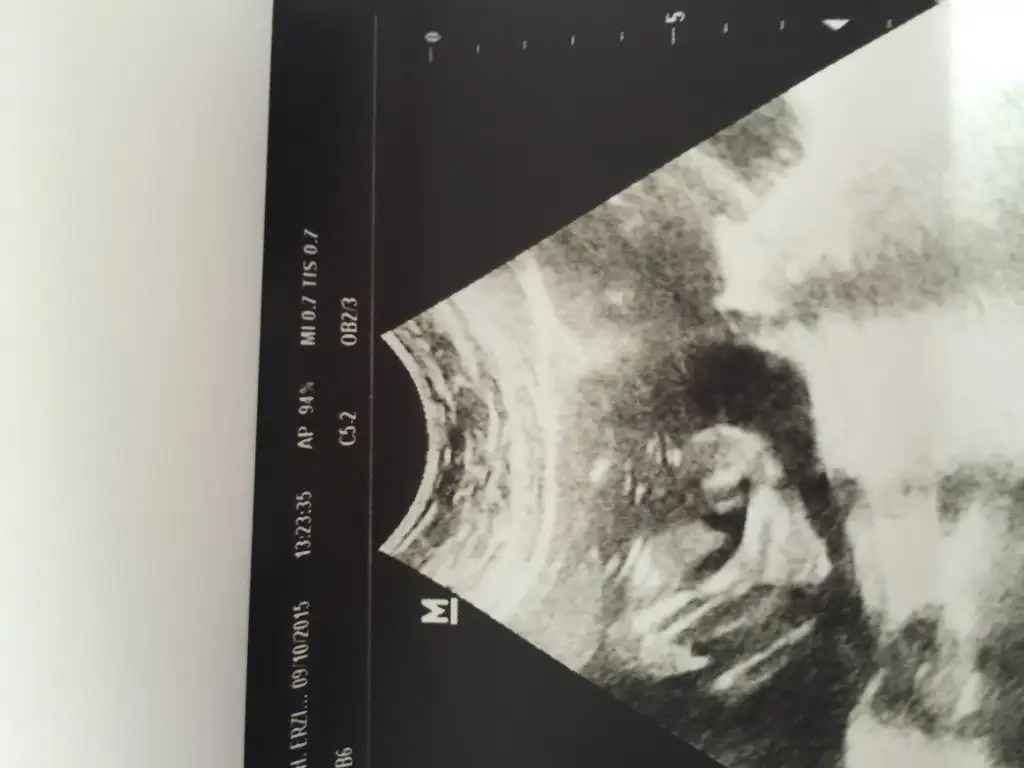

Baya belli tam bir erkek☺

Di mi ama :) bacak vs göremeyince bilemiyo insan ama zaten sadece genital kısmı çekti ondan heralde bakın ikizlerim olcak erkek olanın resmini yüklemiştim kız olan da dümdüz hiç çıkıntı yok